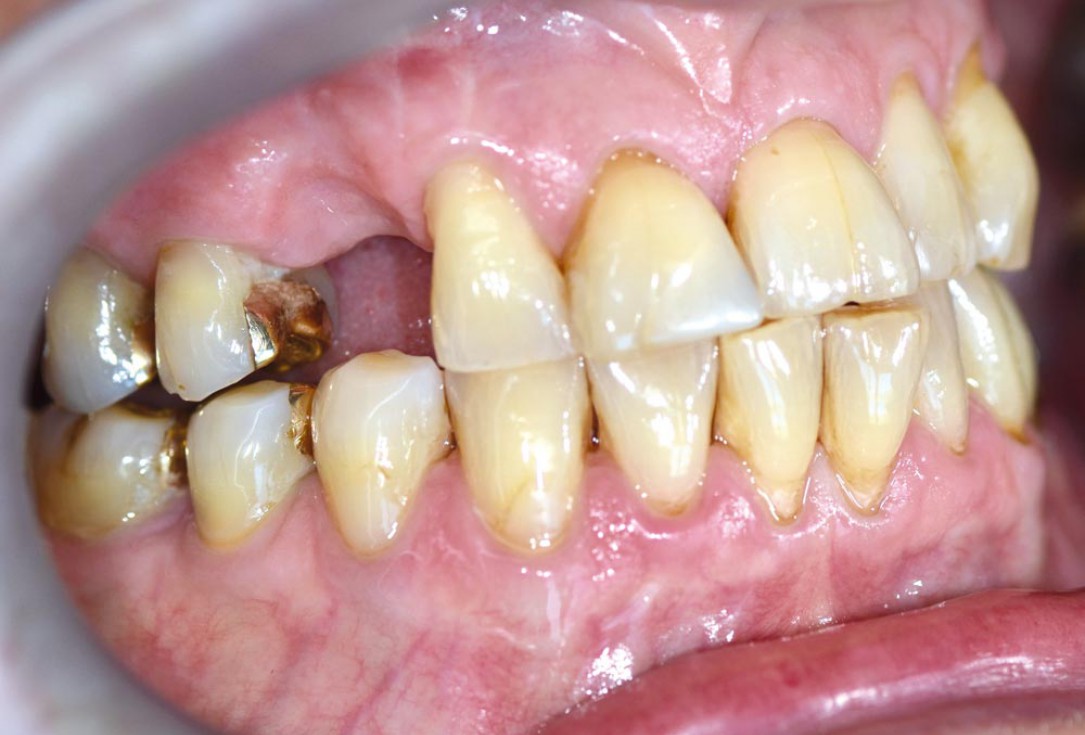

01/12 - Initial situation - bone defect in maxilla after loosing right canine

Block augmentation with maxgraft® in the maxilla - PD Dr. Dr. F. Kloss